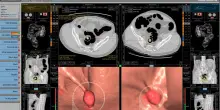

Cancro retto, italiani su Lancet: "25% pazienti può guarire senza chirurgia"